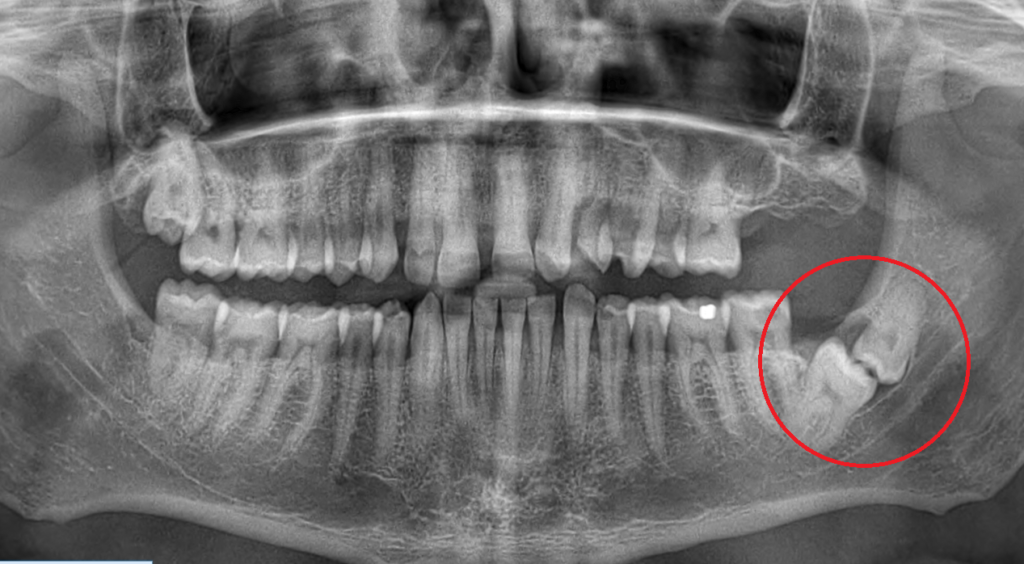

Bölcsességfog eltávolítás

A bölcsességfog eltávolítása mindennapi szájsebészeti eljárásnak számít.

A rossz irányba növekvő, impaktált (nem előtörő bölcsességfog) vagy fogszabályozás céljából a bölcsességfog szájsebészeti eltávolítása indokolt.